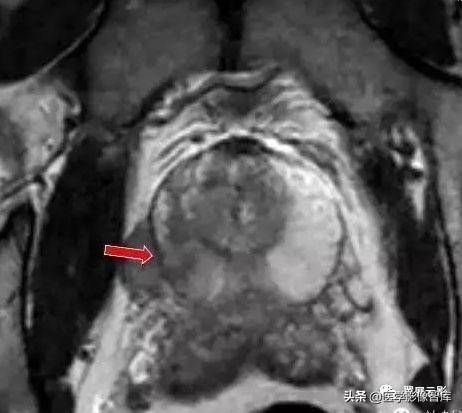

前列腺癌

前列腺癌是最常见男性肿瘤之一,其发病率仅次于肺癌,占男性癌症死因的第2位,前列腺癌70%—75%发生于前列腺的周边带;原发于移行区者,往往与BPH伴发,前列腺癌的转移途径有直接浸润,血行转移和淋巴转移,可侵及尿道,精囊,膀胱,骨转移是最常见的血行播散,其部位依次为骨盆,腰椎,股骨,胸椎,肋骨。

前列腺癌病灶主要在T2WI上进行观察,主要表现为高信号的周围带中出现结节状或片状低信号影,同时应观察前列腺包膜是否完整,周围的脂肪内是否有信号减低的浸润改变,双侧精囊腺大小,精囊三角是否对称,精囊腺信号是否异常也应观察描述,此为观察精囊腺受侵情况。应该注意的是T2WI上周边带低信号非前列腺癌的特异表现,有些少见病变如炎症,瘢痕,钙化也可有类似表现,因此,前列腺癌的MRI诊断需要结合临床及活检。